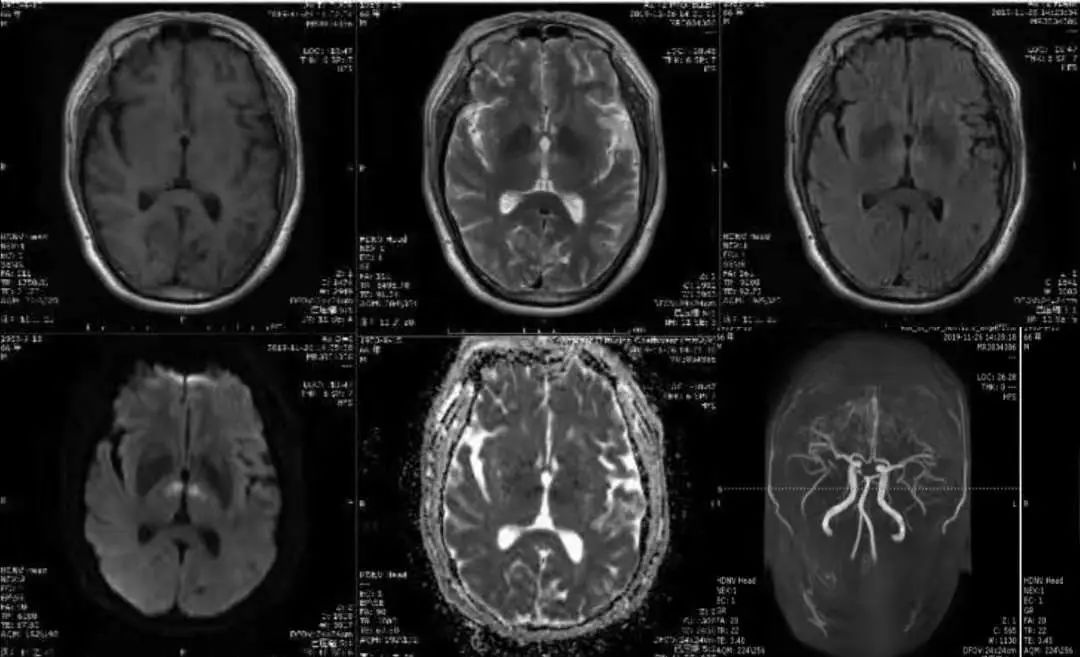

男性,37岁,因反复头痛2年,加重伴视物不清3个月入院。

答案:细胞型血管母细胞瘤,Von Hippel—Lindau综合征(VHL综合征)。

本例晨读时即使隐藏了磁共振平扫T2相,也依然没有逃过老师们的分析判断。血管母细胞瘤根据影像特点分为3种类型:大囊小结节型、单纯型及实质型。大囊小结节型最为常见,结节在MRI呈等信号,增强扫描结节明显强化而囊壁不强化。实质肿块型在T2WI序列呈不均质高信号,瘤周水肿明显,瘤内/瘤周多见血管影可作为重要提示,增强扫描显著强化。

VHL综合征的临床特征为发生于神经系统或视网膜的血管母细胞瘤、肾脏透明细胞癌、嗜铬细胞瘤以及肝、肾、胰腺、附睾等多发囊肿或肿瘤。当发现中枢神经系统血管母细胞瘤时要进一步想到Von Hippel-Lindau综合征的可能。